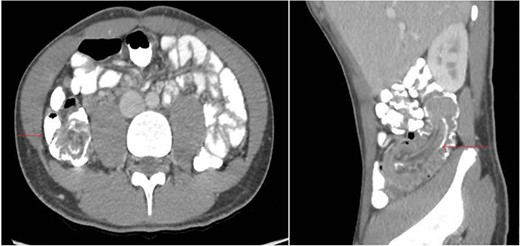

A 17-year-old male presented to the Emergency Department with a 4-day history of abdominal pain localized to the peri-umbilical area. The patient started experiencing the symptoms 3 days before the presentation. The pain was colicky, accompanied by multiple episodes of vomiting and diarrhea. The patient had a previous history of NHL at the age of 4, which manifested as neck mass. He had undergone six cycles of chemotherapy and had been in remission without any signs of relapse until his current presentation. The patient had no significant family history. The patient was conscious and stable at the time of presentation. On physical examination, the patient had tenderness in the right lower quadrant. The patient’s laboratory results were unremarkable: hematocrit was normal, white blood cell count was 6.77 × 103/μL, C-reactive protein level was 0.41 mg/dL, creatinine level was 0.59 mg/dL, urea level was 21 mg/dL, and aspartate aminotransferase level was 15 U/L. CT Abdomen revealed non-obstructive ileocolic intussusception extending for 10 cm with a soft tissue lesion at the tip of the intussusceptum concerning underlying lead point with reactive mesenteric lymph nodes (Fig. 1).

CT Abdomen (axial and sagittal plane) showing ileocolic intussusception extending for 10 cm with a soft tissue lesion at the tip of the intussusceptum concerning underlying lead point with reactive mesenteric lymph nodes.